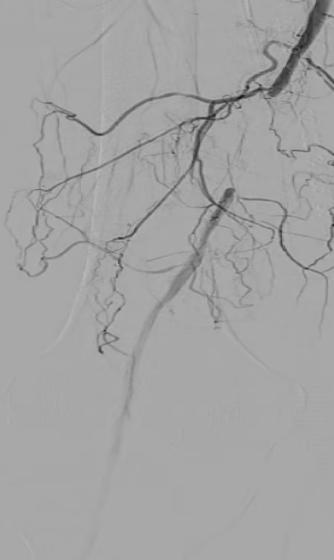

图1 术前股浅动脉下段闭塞

蔺先生这两年过得并不轻松,倍受“右腿走走就疼,休息就好”的怪病困扰。这种医学上称为“间歇性跛行”的症状,近期更是变本加厉,他的脚趾开始出现水泡,疼痛难忍。来到医院后,检查结果令人担忧,作为一名多年糖尿病患者,蔺先生的下肢动脉已经“危机四伏”。特别是右侧股浅动脉出现了闭塞,且血管壁伴有严重钙化。如果把血管比作家里的水管,那里面不仅堵满了淤泥,还结了一层厚厚硬硬的“水垢”,导致血流严重受阻,肢体面临坏死的风险。

面对如此棘手的病例,传统的手术“侦察兵”——数字减影血管造影(DSA)却显得有些力不从心。DSA虽然能看到血流的走向,但呈现的是二维平面图像,就像一张黑白照片,只能看到血管轮廓,无法透视血管壁内的真实结构。对于血管壁的厚度、钙化的程度以及斑块的性质,医生往往只能靠经验去“猜”。在蔺先生这种重度环周钙化的情况下,盲目操作极易导致血管夹层甚至破裂。这时,血管内超声技术(IVUS)便大显身手,它就像是送入血管内部的“天眼”和“GPS”。